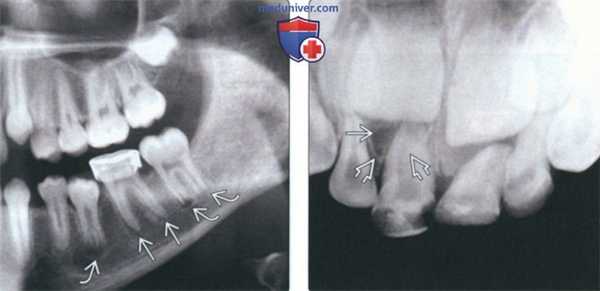

(Слева) При аксиальной КТ в костном окне визуализируется мелкая периапикальная радикулярная киста возле корня центрального резца верхней челюсти справа. Признаков периостальной реакции или наличия объемного образования в мягких тканях за пределами челюсти не определяется.

(Справа) При сагиттальной КТ у этого же пациента визуализируется периапикальная киста и стоматологическая амальгама в этом же зубе.

4. Рентгенография:

• На рентгенограммах зубов можно хорошо различить:

о Кисту, отграниченную кортикальным слоем, у верхушки корня о Отсутствие плотной пластинки

о Расширение пространства периодонтальной связки

• Невитальный зуб, пораженный кариесом, с признаками поражения периодонта, резорбцией корня

(Слева) При сагиттальной КТ в коаном окне в области апикального отверстия корня первого премоляра нижней челюсти справа визуализируется однокамерная киста, хорошо отграниченная от окружающих тканей кортикальной пластинкой. Киста тесно прилежит к твердой пластинке и пространаву периодонтальной связки, что свидетельствует о ее воспалительной природе.

(Справа) При сагиттальной КТ в костном окне в верхней челюсти визуализируется периапикальная киста среднего размера, целостность ее верхней стенки на ограниченном участке нарушена. Определяются также признаки ассоциированного с кистой верхнечелюстного синусита одонтогенного характера.